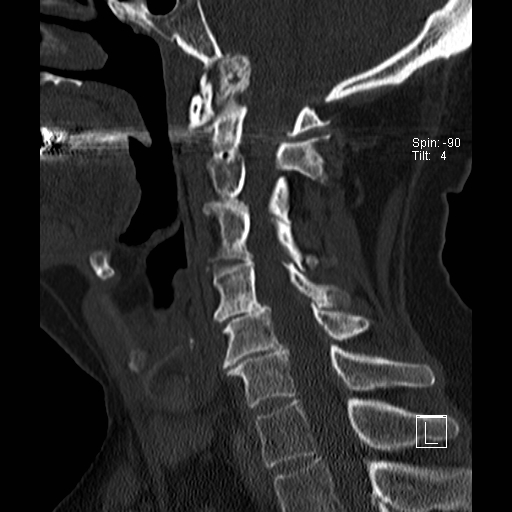

Lồng nền sọ

Lồng nền sọ, còn gọi là sụt lún sọ não hay ấn nền sọ, xảy ra ở 5-10% bệnh nhân viêm khớp dạng thấp cột sống cổ.

Trong lồng nền sọ, mỏm răng sa vào lỗ chẩm làm thu hẹp không gian dành cho tủy sống.

Biểu hiện lâm sàng đa dạng, từ đau đầu mạn tính, hạn chế vận động cổ đến suy giảm thần kinh cấp tính (chèn ép tủy sống và thân não, có thể dẫn đến liệt hoặc thậm chí tử vong nếu cổ bị di chuyển ở một số tư thế nhất định).

Hình ảnh

Cuộn xem các lát cắt CT.

Có hình ảnh di chuyển lên trên của mỏm răng vào lỗ chẩm.